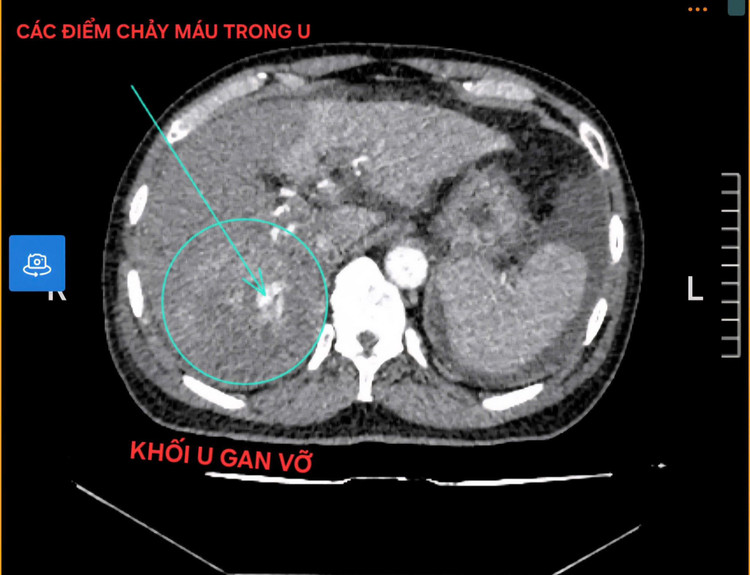

U gan 10cm vỡ, gây xuất huyết ổ bụng

Bệnh nhân nam có tiền sử uống rượu nhiều năm, nhập viện với biểu hiện đau vùng hạ sườn phải, mạch nhanh, huyết áp tụt, dấu hiệu mất máu cấp. Kết quả Chụp cắt lớp vi tính cho thấy có khối u gan kích thước khoảng 10cm đã vỡ, gây xuất huyết ổ bụng trên nền gan xơ. Đây là biến chứng nặng của ung thư gan, có nguy cơ tử vong cao nếu không được xử trí kịp thời.